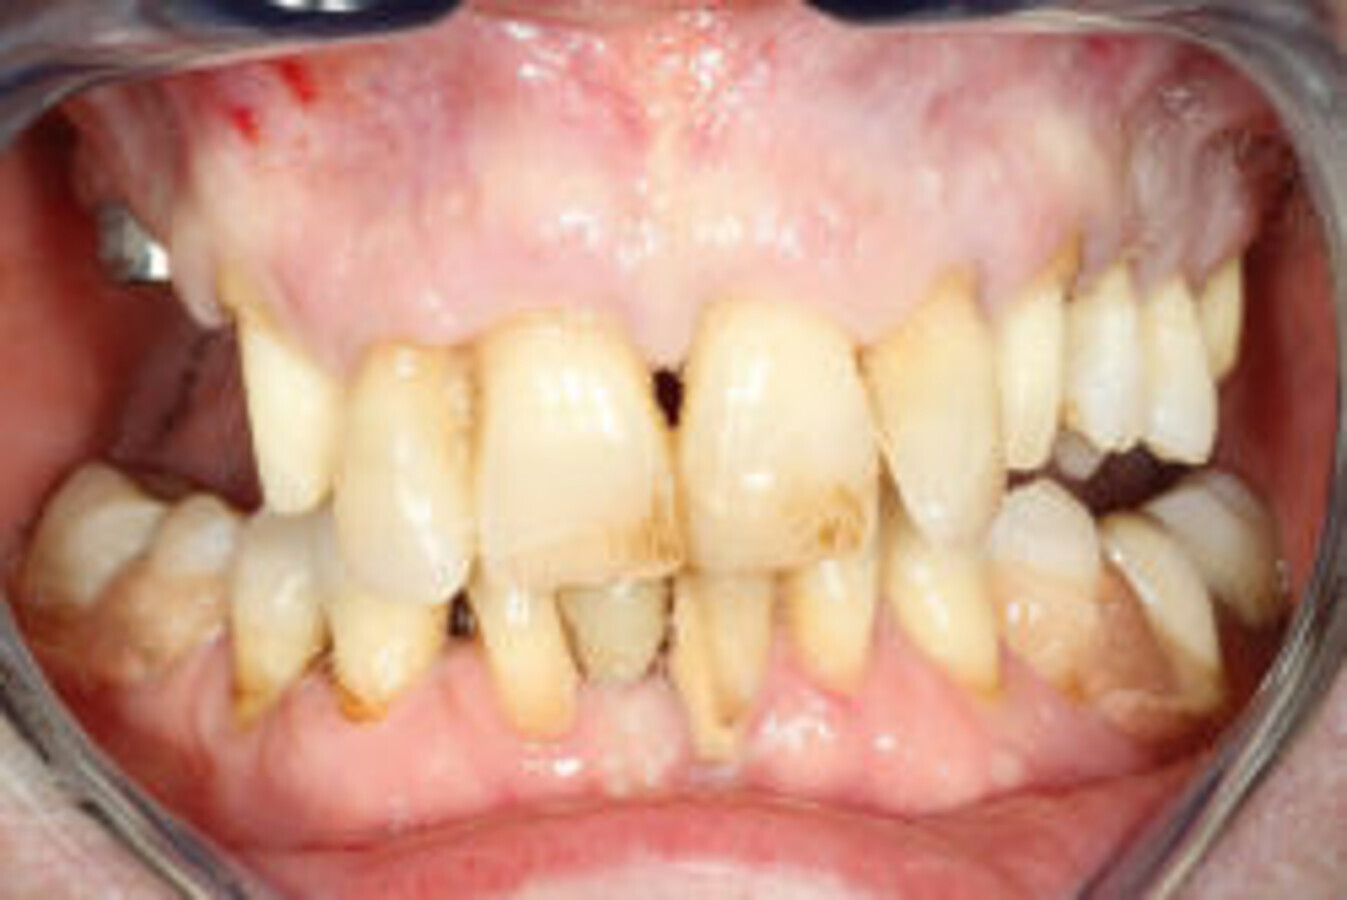

Slika 1: Početna situacija kod pacijenta – ekstraoralno.

Slika 2: Početna situacija kod pacijenta – intraoralno.

58-godišnjakinja, nepušačica i sistemski zdrav pacijent kojeg je njen doktor dentalne medicine uputio u naš centar radi implanto-protetske terapije. Pacijenticu je uglavnom smetala loša estetika u gornjem frontalnom području, koje je karakterizirala visoka linija osmijeha i izražene anomalije položaja zuba (Slike 1. i 2.), kao i funkcionalna ograničenja kao posljedica neugode prilikom žvakanja. Tri zuba su nedostajala u gornjoj distalnoj regiji i to zubi 17, 15 i 27 koji nisu bili protetski opskrbljeni, dok je u donjoj čeljusti u distalnoj regiji nedostajalo pet zuba s obje strane u području premolara te su oni zamijenjeni djelomičnom mobilnom protezom. Svi preostali zubi u gornjoj i donjoj čeljusti bili su prema klasifikaciji „Proceedings of the World Workshop on the Classification of Periodontal and Peri-implant Diseases and Conditions 2017“ imali parodontitis stadija IV, a prosječna dubina sondiranja parodonta je bila 5,6 mm. 7 Prosječni indeks krvarenja (BOP) i srednji indeks plaka (PI) bili su 70 odnosno 80 posto. S obzirom na paradontološke parametre i mjere oralne higijene (vidljivi kamenac i naslage), oralna higijena pacijentice klasificirana je kao loša. Pacijentica je u drugoj ordinaciji liječena s dva implantata u desnoj maksilarnoj stražnjoj regiji kako bi se zamijenili prvi pretkutnjak i prvi kutnjak (Slika 3). Prema definiciji koju je Weißgold uveo 1977. godine, pacijent ima debeli biotip. 26